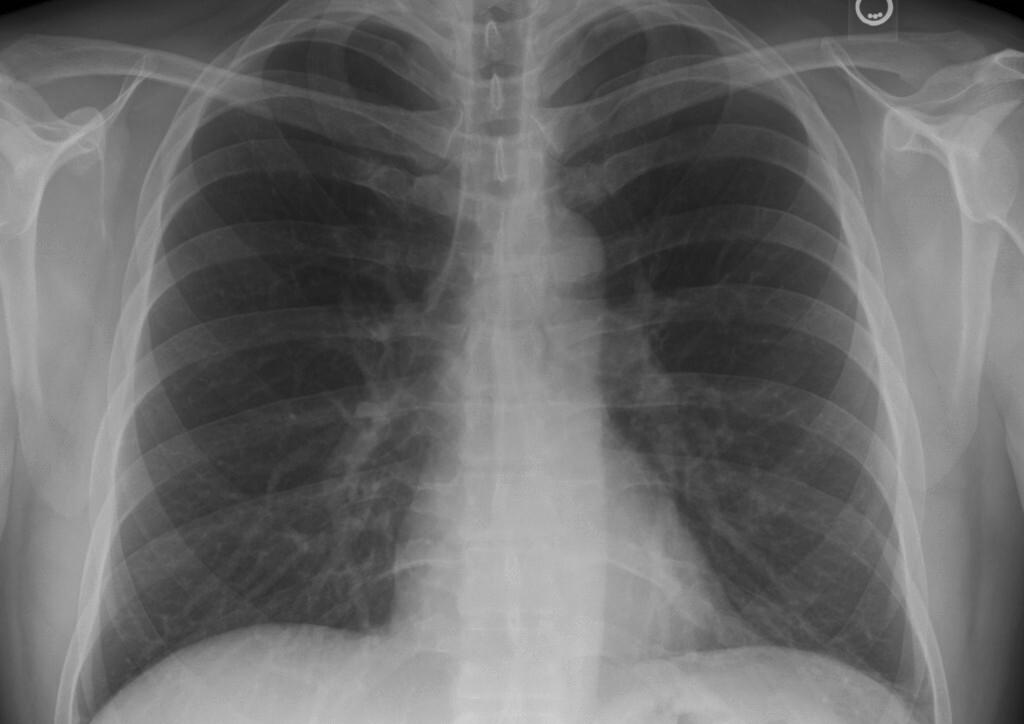

La radiographie thoracique permettrait-elle de réduire la prescription d'antibiotiques en cas de suspicion de pneumonie communautaire ? Pour répondre à cette question, une équipe de l’université Paris Cité et de l’INSERM ont réalisé une étude prospective [1] auprès de 3 729 médecins généralistes.

Pour cette analyse, les chercheurs leur ont attribué des vignettes de patients présentant une suspicion clinique de pneumonie communautaire avec plusieurs scénarios. 2 472 ont été affectés au groupe « radiographie thoracique comme test de première intention » (1 238 avec une « radiographie thoracique négative » et 1 234 avec « radiographie thoracique positive »), parmi lesquels 71,4 % ont prescrit des antibiotiques, contre 90,2 % des 1 257 médecins généralistes affectés au groupe « pas de radiographie thoracique », soit une réduction de prescription de 21 %. Parmi les 1 238 médecins généralistes affectés au groupe « radiographie thoracique négative », la réd